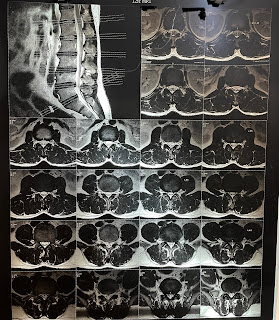

MRI